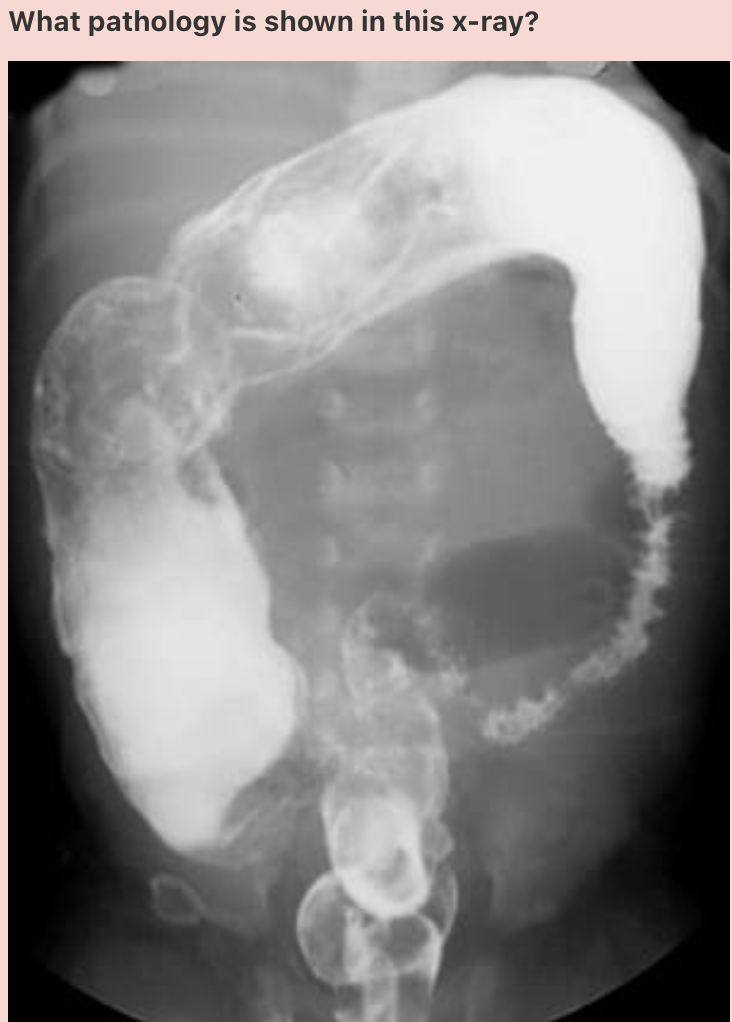

Answer: Duodenal atresia

The double bubble sign is seen in infants with duodenal atresia, and represents dilatation of the proximal duodenum and stomach. It is seen in both radiographs and ultrasound imaging, and can be identified antenatally.